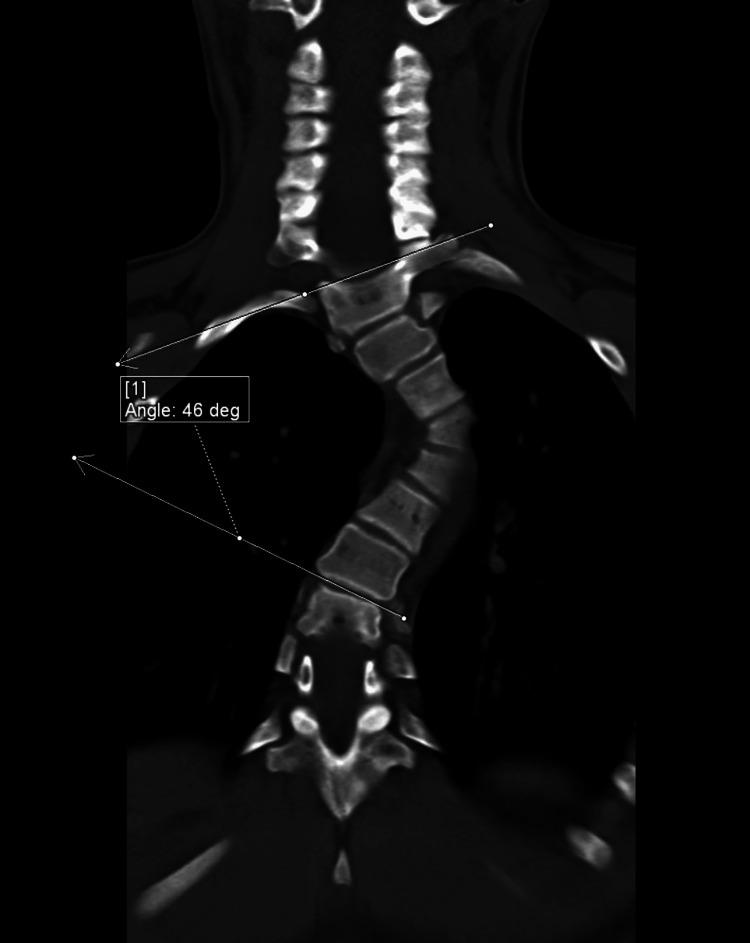

Neurofibromatosis type 1 (NF1) is frequently associated with a multitude of skeletal abnormalities including dystrophic scoliosis. A rare but severe complication of dystrophic scoliosis in NF1 is the herniation of rib heads into the spinal canal, potentially leading to devastating spinal cord compression. We present two pediatric cases of NF1-associated dystrophic scoliosis with intra-spinal herniation of rib heads. Case 1 involves a teenage male with progressive thoracolumbar scoliosis and protrusion of T10 and T11 rib heads into the spinal canal, who underwent successful posterior spinal fusion (T3-L3) with instrumentation, osteotomies, and rib head resection. Case 2 involves a teenage female with progressive thoracolumbar scoliosis and intra-spinal protrusion of T4 and T5 rib heads, who remains neurologically intact despite worsening curvature. Intra-spinal herniation of rib heads is a clinically important complication of NF1-associated dystrophic scoliosis requiring close surveillance. Familiarity with this complication is important as imaging findings may be subtle early on. Surgical management typically involves both spinal fusion and resection of rib heads to prevent neurological compromise, though timing may vary based on symptoms and progression. Multidisciplinary care is essential.

1型神经纤维瘤病(NF1)常伴有多种骨骼异常,包括营养不良性脊柱侧凸。NF1中营养不良性脊柱侧凸的一种罕见但严重的并发症是肋骨小头疝入椎管,可能导致毁灭性的脊髓压迫。我们报告两例NF1相关的营养不良性脊柱侧凸伴肋骨小头椎管内疝的儿科病例。病例1为一名青少年男性,患有进行性胸腰椎脊柱侧凸,T10和T11肋骨小头突入椎管,接受了成功的后路脊柱融合术(T3-L3),包括器械固定、截骨术和肋骨小头切除术。病例2为一名青少年女性,患有进行性胸腰椎脊柱侧凸,T4和T5肋骨小头椎管内突出,尽管脊柱侧凸加重,但神经功能仍保持完好。肋骨小头椎管内疝是NF1相关的营养不良性脊柱侧凸的一种重要临床并发症,需要密切监测。熟悉这种并发症很重要,因为早期影像学表现可能很细微。手术治疗通常包括脊柱融合和肋骨小头切除,以防止神经功能受损,不过手术时机可能因症状和病情进展而异。多学科护理至关重要。